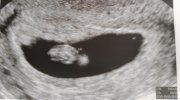

Trzymam kciuki za piękne bicie serca maluszkaDziewczyny za godzinę mam wizytę " serduszkową" jestem przerażona tak bardzo się stresuje ,że aż boje się siadać za kierownicą .Dla towarzystwa jedzie ze mną siostra i wiecie co chyba zabieram ją żeby mieć wsparcie jak usłyszę coś złego ....Chyba ciąża po poronieniech po prostu już tak wygląda .

Kamień z serca ,całe 8mm człowieka i bijąceTrzymam kciuki za piękne bicie serca maluszka![]()

Piękne wiadomości <3Kamień z serca ,całe 8mm człowieka i bijące. Wielkość zarodka zgadza się z wiekiem ciąży na tą chwilę wszystko dobrze .Siedzę i ryczę ze szczęścia .